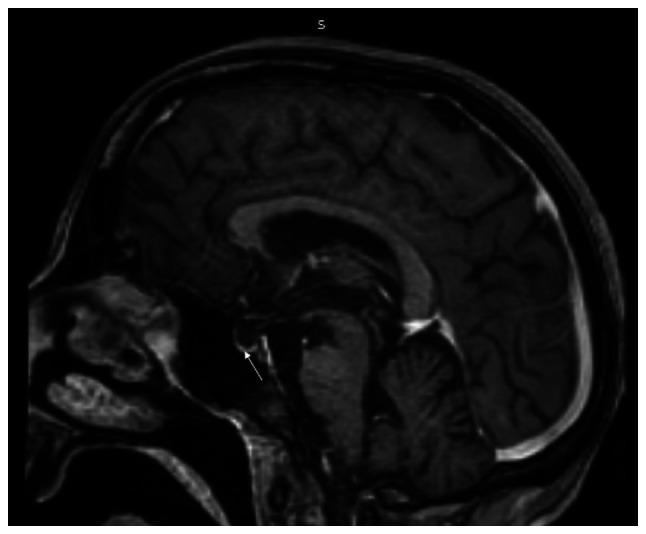

Both myxedema crisis and Sheehan's syndrome are uncommon conditions. The first-time presentation as myxedema crisis is rare in Sheehan's syndrome. The present study describes the case of a 31-year-old female patient who presented with altered sensorium in the emergency room. The patient was not a known case of hypothyroidism, but had a history of secondary amenorrhea and lactation failure following the birth of a child 11 years prior. Upon evaluation, she was found to have hypothermia, hypotension, the delayed relaxation of deep tendon reflexes, bradycardia and hyponatremia, which led to the suspicion of myxedema crisis. Her thyroid function tests were suggestive of secondary hypothyroidism and her pituitary hormonal profile revealed panhypopituitarism. The patient was managed on the lines of myxedema crisis with oral levothyroxine, hydrocortisone infusion, antibiotics and rewarming. Her clinical and biochemical parameters exhibited an improvement; however, her altered sensorium persisted. A repeat neurological examination revealed cogwheel rigidity with paraparesis, which led to the clinical suspicion of acute parkinsonism. Magnetic resonance imaging of the sella and brain was suggestive of an empty sella and extrapontine myelinolysis, substantiating the diagnosis of Sheehan's syndrome with acute parkinsonism. The patient was commenced on levodopa-carbidopa following which there was an improvement in symptoms. The patient improved over the ensuing 6 months and can now perform all household activities. On the whole, the present study indicates that the early suspicion of myxedema crisis, prompt treatment and the recognition of additional aetiology for persistent altered sensorium can result in a successful outcome for the patient.

黏液水肿危象和希恩综合征均为罕见病症。以黏液水肿危象首次发病在希恩综合征中较为罕见。本研究描述了一名31岁女性患者的病例,该患者在急诊室出现意识改变。患者既往并非已知的甲状腺功能减退病例,但有11年前分娩后继发性闭经和泌乳失败的病史。经评估,发现她体温过低、血压低、深腱反射弛缓延迟、心动过缓和低钠血症,这引发了对黏液水肿危象的怀疑。她的甲状腺功能检查提示继发性甲状腺功能减退,垂体激素检查显示全垂体功能减退。该患者按照黏液水肿危象的治疗方案进行管理,给予口服左甲状腺素、氢化可的松输注、抗生素和复温治疗。她的临床和生化指标有所改善;然而,她意识改变的情况仍然存在。再次进行神经检查发现齿轮样强直伴双侧下肢轻瘫,这导致临床怀疑为急性帕金森病。蝶鞍和脑部的磁共振成像提示空蝶鞍和脑桥外髓鞘溶解,证实了希恩综合征合并急性帕金森病的诊断。患者开始服用左旋多巴 - 卡比多巴,此后症状有所改善。患者在接下来的6个月中逐渐好转,现在能够进行所有家务活动。总体而言,本研究表明,早期怀疑黏液水肿危象并及时治疗,以及识别意识持续改变的其他病因,可为患者带来成功的治疗结果。